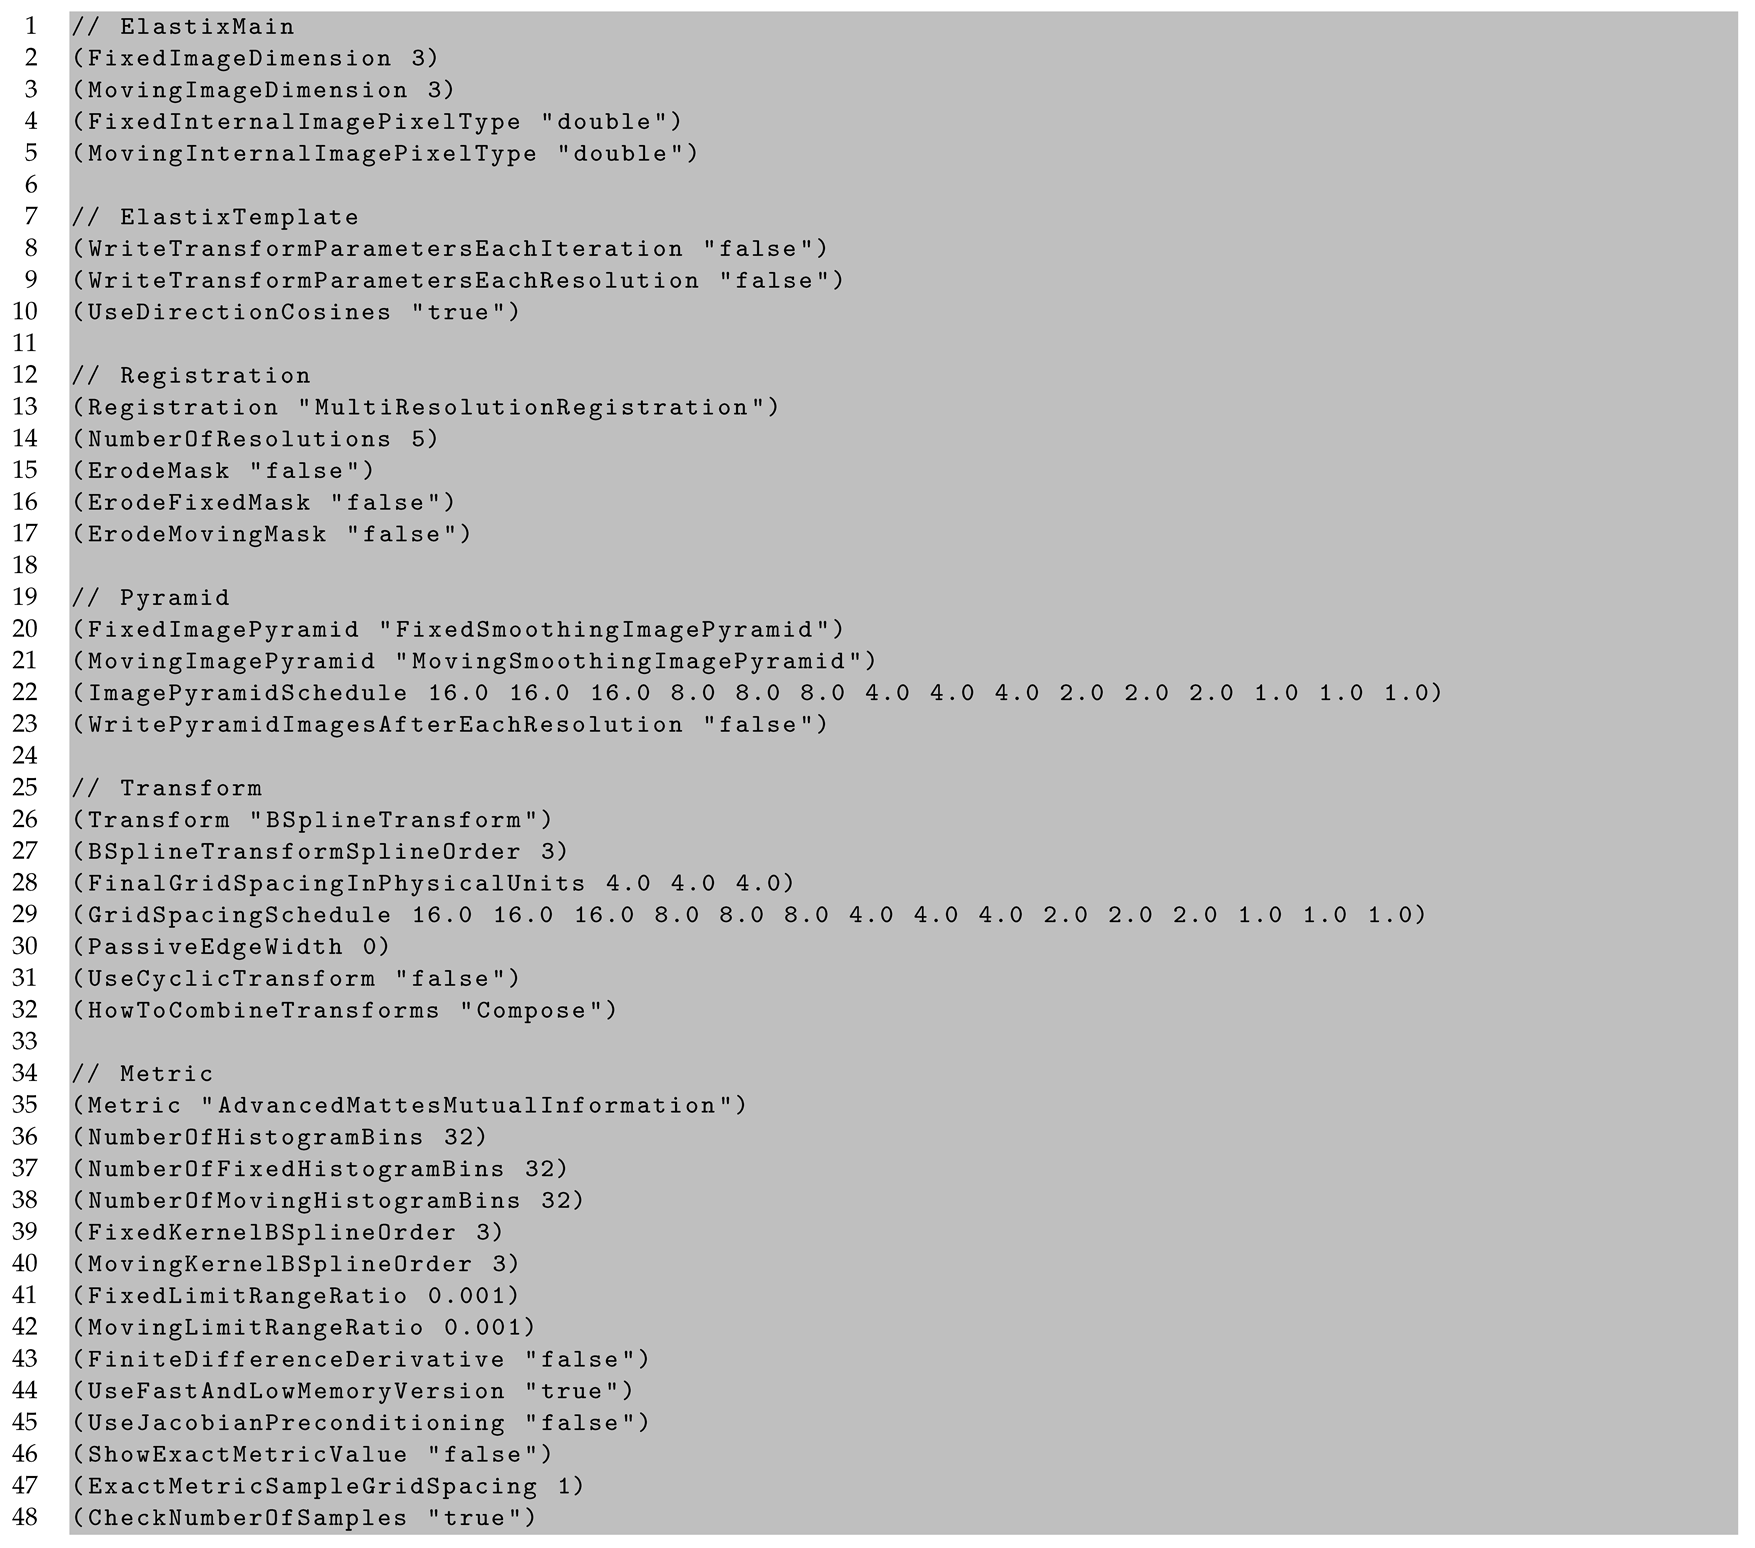

2.6. Cell Density Maps to Ex Vivo T1 Registration

Appendix C. In Vivo to Ex Vivo Registration